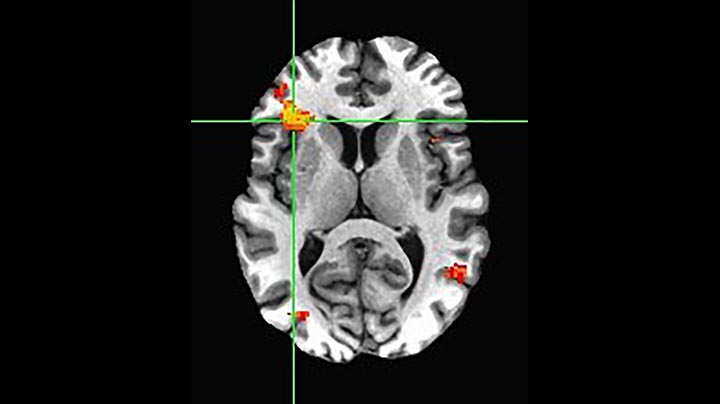

BOLD fMRI activation, depicted in color, of left anterior insula (MNI plane z = 8 mm) in a single subject by a contrast between viewing and matching faces with negative emotion (angry, sad, scared) versus happy faces. The voxelwise threshold is p < 0.001, and colored voxels survive false discovery rate correction to p < 0.05. The activated voxels in color are overlaid on the subject's own 3D-TFE image displayed in grayscale, after transforming the data to MNI space. The fMRI pulse sequence was a single shot FFE echo planar acquisition using MultiBand SENSE factor 6, dS SENSE factor 1, isotropic voxel size 2.4 mm, 60 transverse slices, TR 950 ms, TE 30 ms, flip angle 52 degrees, 517 dynamic scans, total scan duration 8:21 minutes. Image provided by James M. Bjork, PhD, Associate Professor of Psychiatry at VCU.